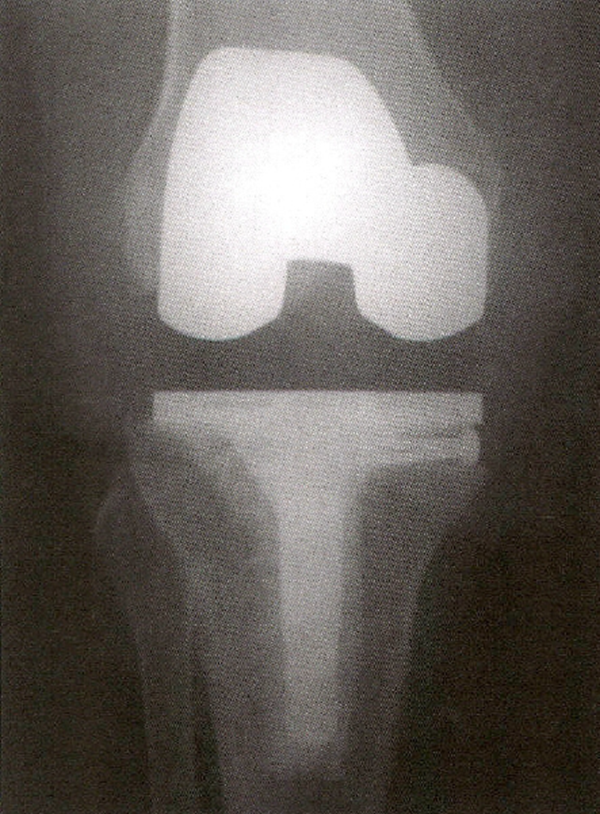

尽管目前在初次置换中常常作为非必要部分多孔金属加强块和锥形袖套的报道应用的效果较好(图5A)。把锥形袖套压配到股骨远端或胫骨近端的包容性骨缺损中,并用骨水泥把假体粘贴于这些加强块上使其成为一体。还可以把锥形袖套和假体组合形成一体式的假体结构。包容性骨缺损中,锥形袖套也可以粘在假体上组合形成单一假体结构。诸如图5BC。这些方法大部分应用于伴有明显骨缺损的翻修手术中。这些锥形袖套的骨整合能力非常好,甚至假体失败后也很难取出。

5 A.将多孔金属锥体放置在干骺端缺损处,以加强固定。B.X线片示用双叶胫骨假体扩大由于胫骨平台骨折不愈合造成的缺损。C.如图所示,类风湿关节炎骨不良患者翻修TKA的正侧位片中,与植入物茎端相连的袖套型假体可以增强骺端包容或非包容性的缺损